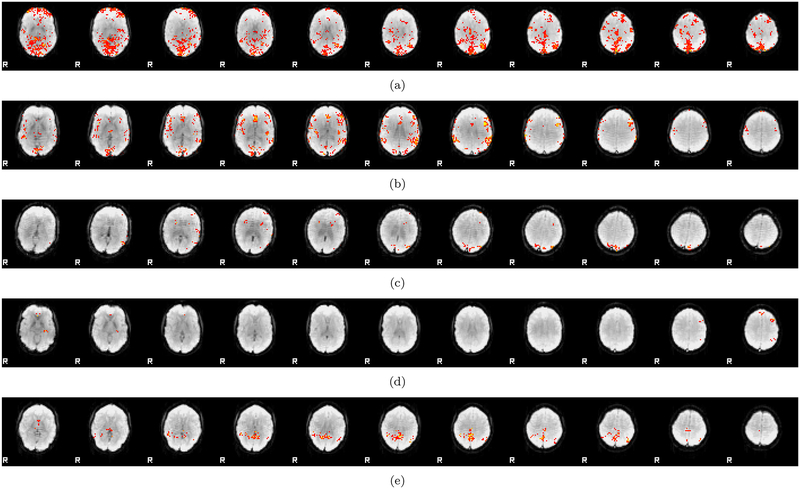

Figure 10:

Activity maps (thresholded at CDT p = 0.01 and cluster FWE corrected at p = 0.05, FSL default) for 5 Oulu subjects analyzed with 4 mm of smoothing and first level design E4. Despite testing for a difference between two random regressors, which are for design E4 also randomized over subjects, significant voxels are in several cases detected close to the superior sagittal sinus (indicating a vein artefact). Since many subjects have an activation difference in the same spatial location, this caused inflated false positive rates for the one-sample t-test. The two-sample t-test is not affected by these artefacts, since they cancel out when testing for a group difference.